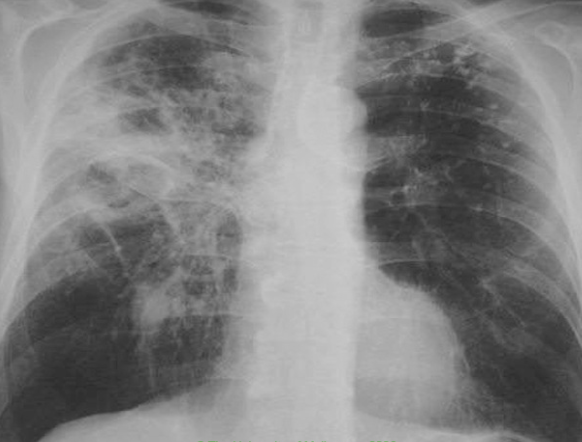

A 78yo male becomes septic following pneumonia. Over the next 24-48 hours, his SOB worsens and his oxygen saturation drops

ARDS

Other causes: aspiration, inhalation injury, acute pancreatitis, trauma, radiation, transfusion reaction, fat embolism, DIC, drug overdose, idiopathic